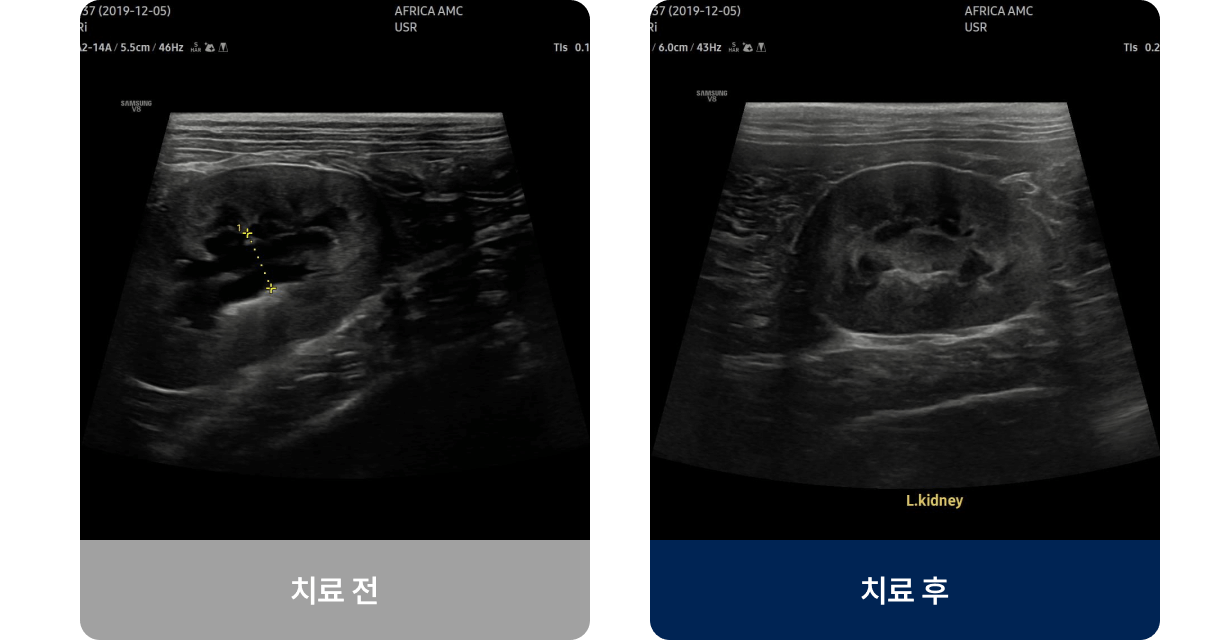

신장센터는 신장의 여과 기능 이상과 요로계 질환을 진단·치료하는 분야입니다. 아프리카 동물의료센터는 신장 전문 의료진이 정밀 검사를 통해 장기 기능을 보호하는 맞춤형 치료 계획을 제공합니다.

신장 질환은 진행 속도가 각기 다르기에 체중·혈압·전해질·수분 균형을 지속적으로 조정하는 관리가 필수입니다. 정기적인 추적 관찰과 개별 치료로 합병증 없이 안정적인 상태를 유지할 수 있습니다.

아프리카 동물의료센터는 질환의 단계, 체중, 생활 습관을 함께 고려해 아이에게 꼭 필요한 약만 최소 용량으로 처방하며, 정기적인 모니터링과 맞춤형 관리로 보호자가 안심할 수 있는 치료 환경을 제공합니다.